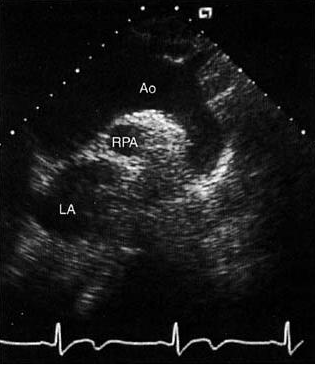

8.主动脉弓长轴切面

Schematic and 2D echo images of the aorta in a long-axis view from the suprasternal notch window. The ascending aortic (Ao) arch and descending thoracic aorta are seen with the origins of the left carotid and subclavian arteries. The right pulmonary artery (RPA) lies immediately inferior to the arch.

主动脉弓长轴切面